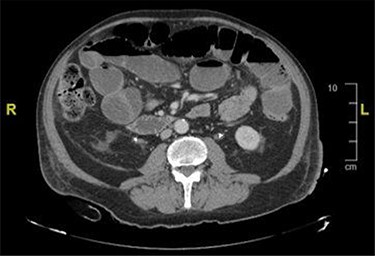

CT and magnetic resonance imaging (MRI) of the abdomen and pelvis indicated that a loop of small bowel was caught up in the pelvic mass resulting in a mechanical small bowel obstruction (Fig. 2).

CT image showing distended bowel loops indicating bowel obstruction caused by the pelvic mass.